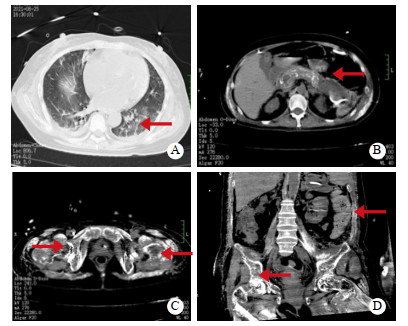

1 资料与方法患者女,44岁,因“上腹部疼痛19 d,意识模糊半个月”由外院转入。患者入院前19 d无明显诱因出现上腹部疼痛,曾在当地县人民医院就诊,诊断为“急性胰腺炎”,经对症支持治疗效果不佳,2021-08-07转往当地市人民医院ICU治疗,具体诊疗不详。2021-08-11患者出现意识模糊、谵妄。2021-08-24转入湖南省人民医院急诊科。入院时患者腹胀、高热,神志谵妄,躁动不安,呼吸急促。既往有泌尿系结石病史6年,曾行2次手术治疗(术式不详)。家族中无胰腺炎及其他特殊病史。入院查体:体温39.3℃,心率150次/min,呼吸35次/min,血压106/68 mmHg(1 mmHg=0.133 kPa)。神志模糊、谵妄,贫血貌,呼吸急促。双肺呼吸音粗,双下肺呼吸音稍减弱,未闻及明显干、湿性啰音。心率律齐,无杂音。腹稍膨隆,腹肌稍紧张,全腹部压痛,叩诊呈鼓音,肠鸣音减弱。左下肢呈外旋、右下肢呈内旋畸形,双髋关节外侧压痛明显。辅助检查:血常规示白细胞计数16.34×109/L↑,血红蛋白80 g/L↓;血生化:白蛋白27.5 g/L,血尿素氮48.27 mmol/L,血肌酐263.3 μmol/L,甘油三酯5.45 mmol/L,血钙3.02 mmol/L,血磷2.15 mmol/L,血钾5.67 mmol/L;血气分析:pH 7.36,PCO2 21 mmHg,PO2 108 mmHg,HCO3- 11.9 mmol/L,BEecf −13.5 mmol/L,Lac 3.3 mmol/L;降钙素原1.84 ng/mL。胸部+腹部CT示:(1)双肺炎症;(2)双肺散在结节,性质待定;(3)双侧胸膜增厚;(4)心包增厚钙化;(5)急性胰腺炎并胰周、左肾周坏死物积聚;(6)双肾多发结石;(7)胸腹部骨质广泛骨质疏松及软组织内广泛钙化灶;(8)双侧股骨近段骨折(疑似病理性)。见图 1。

| A:双肺炎症,双肺散在结节,双侧胸膜增厚,心包增厚钙化;B:急性胰腺炎并胰周、左肾周坏死物积聚,胰腺多发钙化灶;C:双侧股骨近段骨折(病理性);D:胸腹部骨质广泛骨质疏松 图 1 患者胸部+腹部CT影像 |